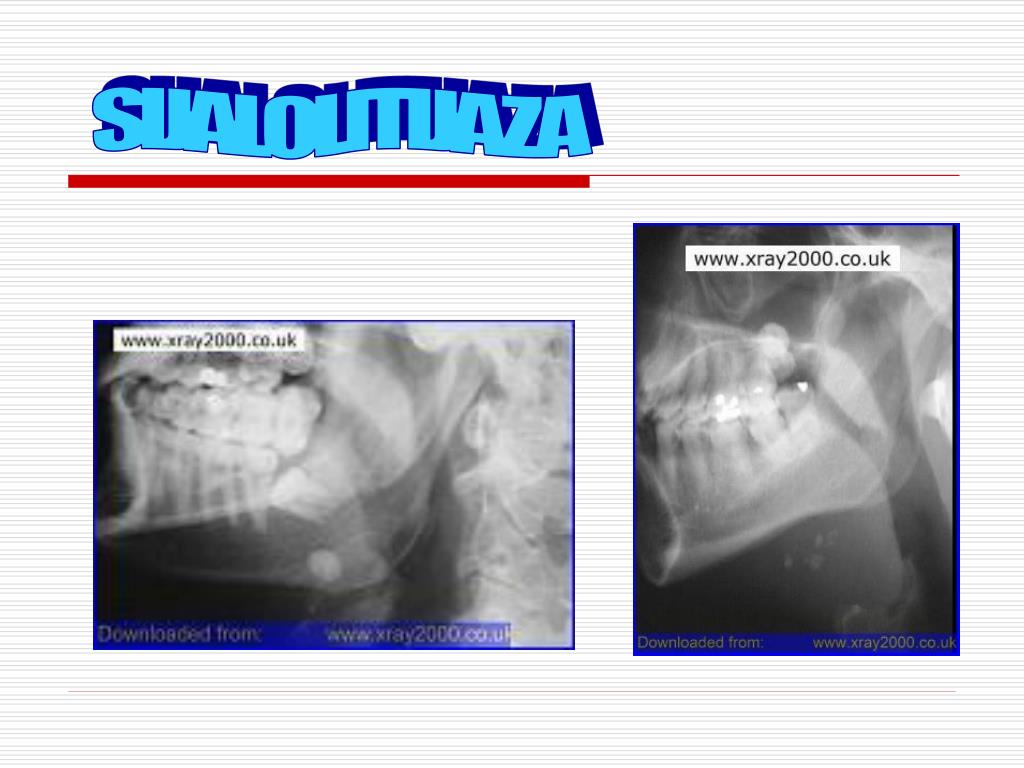

12. SIJALOLITIJAZA

13. SIJALOLITIJAZA

14. SIJALOLITIJAZA Ca fosfat 74% Ca karbonat 11% ostalo